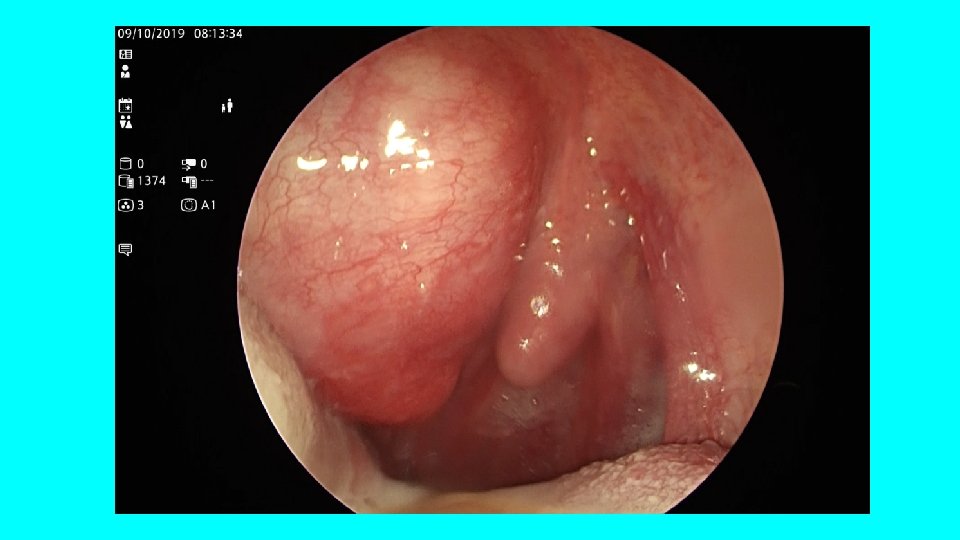

ASCESSO PERITONSILLARE

ESAME OBIETTIVO Ugola ? ? ? Loggia tonsillar e sinistra